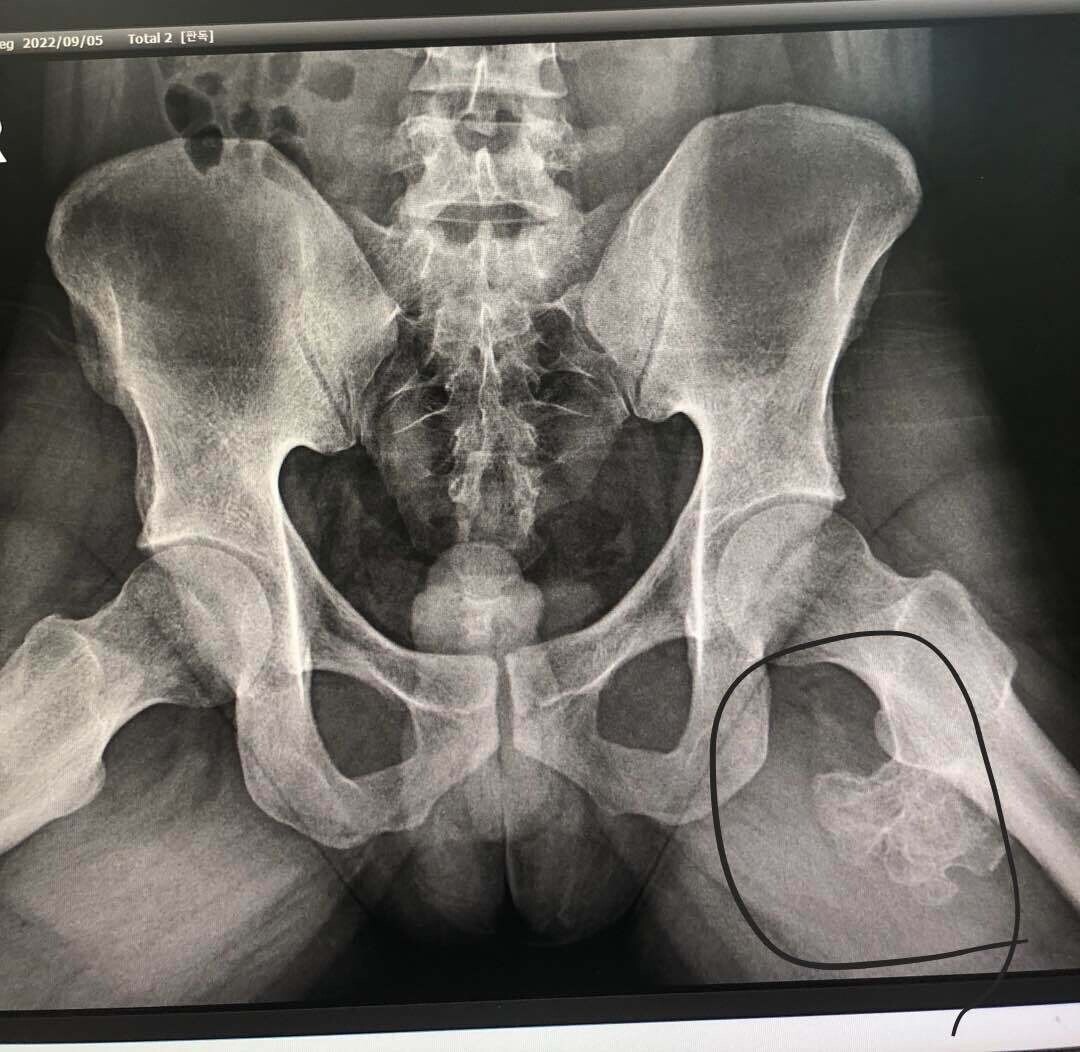

23살 남동생이 언제부터 엉덩이 밑? 저기가 아프다 했고

오늘 동네 정형외과 갔더니 종양? 이라고 대학병원가서 mri찍고 조직검사하래,,,

동생이 1살? 2살? 때

신장암으로 수술하고 항암 했던 이력이 있긴한데